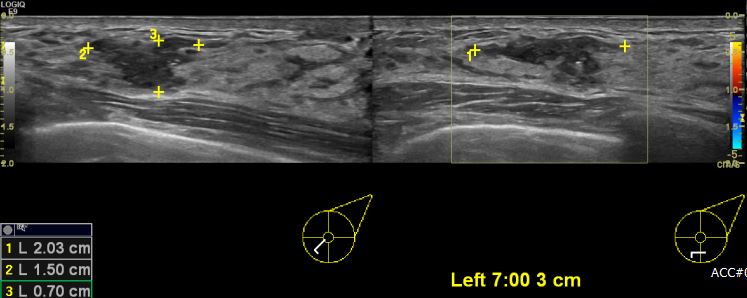

유두 분비물로 내원하신 40대 여성 분으로 좌측 유방 7시 방향에서 3cm  떨어진 거리의

의심스러운 멍울 조직검사 시행하여 좌측 유관암 진단 되었습니다.